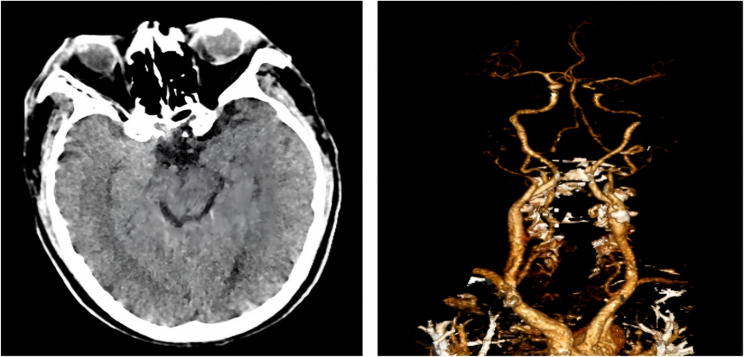

男性,64岁,表现为急性左肢体无力,脑CT灌注成像未见异常。患者很快出现心脏骤停,心肺复苏成功后冠状动脉造影显示前降支和旋支中段完全闭塞,右侧冠状动脉中段弥漫性病变。非典型AMI表现使急诊诊断复杂化,需要高度的临床警惕和在初步评估时进行广泛的鉴别评估。

A 64-year-old man presented with acute left-sided limb weakness and no abnormalities on brain CT perfusion imaging. The patient soon experienced cardiac arrest, and coronary angiography after successful cardiopulmonary resuscitation demonstrated complete occlusion of the anterior descending branch and circumflex branch mid-sections, as well as diffuse lesions in the right coronary mid-section. Atypical AMI manifestations complicate emergency diagnosis, necessitating high clinical vigilance and broad differential assessment during initial evaluation.